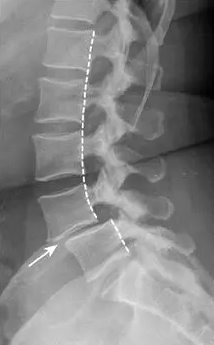

전방전위증으로 척추뼈가 어긋난 상태는 X-ray 검사에 잘 나타나기 때문에 진단하기는 어렵지 않다. 하지만 증상이 심한 환자는 신경이 얼마나 눌렸는지, 수술적 치료를 해야 하는지, 어떤 범위를 수술해야 하는지 등을 결정하기 위해서 MRI 검사를 하는 것이 좋다.